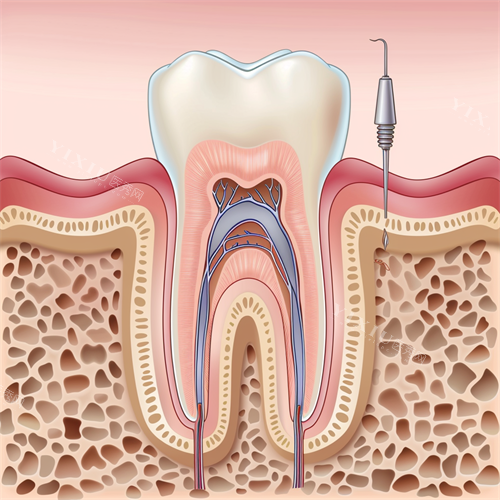

这家位于东城新区的诊所堪称“硬件控”的首要选择。引进了智能化口腔扫描仪、不痛麻醉系统等靠前设备,能通过3D建模模拟矫正结果,让患者提前看到牙齿移动轨迹。

依托地理优势,这家紧邻郯子湖公园的门诊部自带文艺形象。其核心竞争力在于强大的医师团队,两位学科带头人曾组织医务人员赴北京、济南等地培训,并引进国内外比较靠前的CBCT全景影像系统和超声骨刀设备。